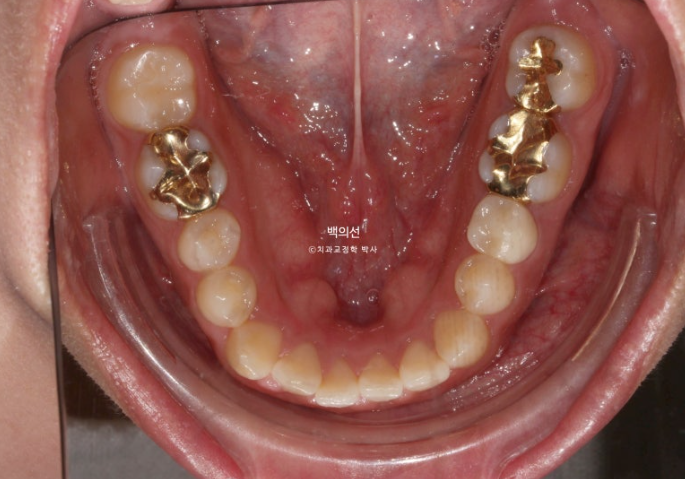

교합면에서 보면 안쪽 맨 뒤 큰어금니 하나가 없는 것이 보입니다.

선천적 결손치아 입니다.